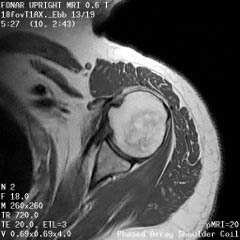

The Prostate without an Endorectal Probe |

The Heart |

![]() |

| Prostate: Delineation of Peripheral Zones (PZ), Cortical Zone (CZ) and Vescicles without an Endorectal Coil. | |

Cervical Spine |

|

Upright Neutral |

Upright Extension |

Unsuspected

Disc Herniation in Extension |

The Liver, Kidney

and Small Intestine

Bladder

and Uterus in Pelvic Floor Dysfunction (PFD) |

Lumbar Spine |

Recumbent, Weightless |

Upright, Weight-Bearing |

Figure 8.

Figure 8a-8d.

Further examples of the exceptional anatomic detail

made visible by the DISCOVERY

of Damadian of the pronounced differences in the decay

rates (relaxations) of the NMR signals

of the body's normal tissues (Figure

6). The DISCOVERED

differences supply the pixel amplitude differences

"PIXEL CONTRAST (IMAGE DETAIL)"

that produce, for the first time in medical history,

the detailed visualization of normal human anatomy

MRI is noted for. Note the visualization of the

vestibular and cochlear nerves

WITHIN

the internal auditory canel (Figure 8b) and the visualization

of the hypothalamic

tract (that transports hormones from

the brain) WITHIN

the pituitary stalk. (Figure 8c)